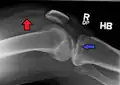

Lipohermatrosis (presencia de grasa y sangre provenientes de la médula ósea en el espacio de la articulación después de una fractura interarticular) visto con Rayos-X en una persona con una leve fractura de meseta tibial. -

Lipohermatrosis debida a una fractura de meseta tibial -